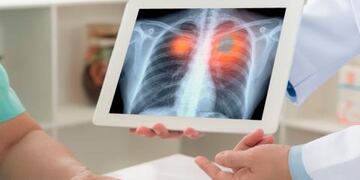

Virtual: Arranca el V Congreso Argentino de Ecocardiografía e Imágenes en Cardiología

El evento organizado por la Federación Argentina de Cardiología, y con el apoyo del Gobierno provincial a través de la Universidad de La Punta, se realizará del 3 al 5 de noviembre.